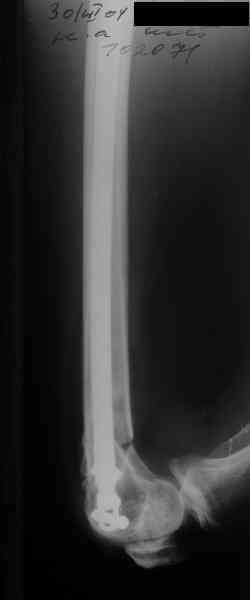

Re: Перелом диафиза и мыщелка бедра

А в чем проблемы? Пример в приложении.

Насчет снимка Вами представленного - смотрится оч красиво, еще бы на функцию узнать...

I> Насчет снимка Вами представленного - смотрится оч красиво, еще бы на

I> функцию узнать...

В приложении функциональные снимки в 3 мес. и в 1 год.